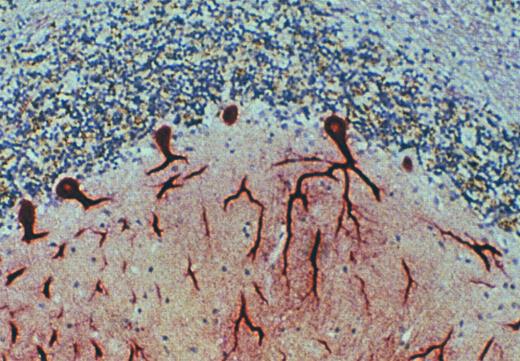

Purkinje cells of the cerebellum express the DARC. Immunohistochemical staining of archival specimens of human cerebellum with the anti-DARC MoAb, anti-Fy6, showed high-level expression of DARC by Purkinje neurons. This staining was inhibited by a recombinant fusion protein in which the amino terminal extracellular domain of DARC was expressed in continuous translational frame with glutathione-S-transferase. Cross-linking experiments with 125I-labeled MGSA and immunoblots with anti-Fy6 showed that MGSA and anti-Fy6 react with a protein component of cerebellar membranes with the same size and appearance on SDS-PAGE as RBC and endothelial cell DARC (data not shown).

Chaudhuri et al105 demonstrated the presence of mRNA in human brain that specifically hybridized with DARC cDNA. Interestingly, there were two species of mRNA observed: one of the predicted size, 1.2 kb, which was also detected in many other tissues tested; and one of 8.5 kb, which thus far has only been observed in brain. Although the nature of the 8.5-kb transcript has not yet been elucidated, the findings of DARC transcripts in the brain prompted our investigation of brain by immunohistochemistry.11,123 Anti-Fy6 was found to react specifically with Purkinje neurons of the cerebellum (Fig 6, see page 3083). Parallel experiments were done with an MoAb against IL-8 receptor B (IL-8RB) which reacted specifically with subsets of neurons in diverse regions of the brain and spinal cord.123 These included the hippocampus, dentate nucleus, pontine nuclei, locus coeruleus, and paraventricular nucleus in the brain and the anterior horn, interomediolateral cell column, and Clarke's column of the spinal cord. Like Purkinje neurons of the cerebellum that express DARC, the neurons in other areas of the brain and spinal cord that express the IL-8RB are projection neurons, bearing long axons that connect one neuronal region with another. Interneurons, which connect neurons within a region, did not react with either anti-Fy6 or the anti–IL-8RB antibody.

Further experiments were performed to confirm that anti-Fy6 reactivity with Purkinje cells was indeed caused by the presence of DARC. Membranes were isolated from cerebellar tissue at postmortem examination and these were analyzed for the presence of DARC by chemokine binding assays, chemokine cross-linking experiments, and immunblotting. Results obtained by each of these methods supported the immunohistochemical data and indicated that DARC is indeed expressed on Purkinje neurons of the cerebellum. What function DARC serves on Purkinje neurons and how this relates to its expression on RBCs and on endothelial cells remains to be determined.